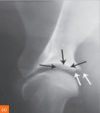

CCLR (Cranial crucial ligament rupture) on radigoraphy. (3)

Can be seen: - Compressed infrapatellar fat pad - Distal displacement of popliteal sesamoid - Osteophyte development if chronic/ time has passed since rupture. Evaluate both sides!

86